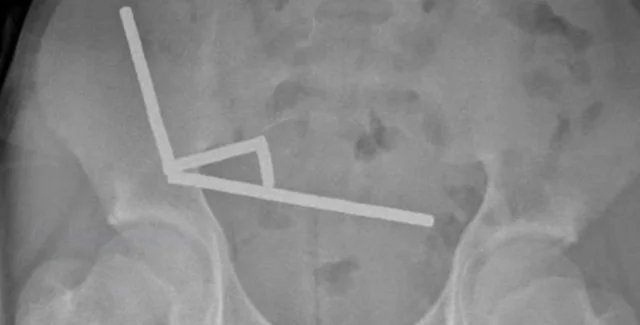

Рентгеновское изображение магнитов в брюшной полости | Фото: ScienceAlert

После того, как врачи сделали рентгеновские снимки брюшной полости подростка, они обнаружили, что в разных отделах кишечника мальчика находятся четыре линейных цепочки из неодимовых магнитов, которые соединились. Мелкие металлические предметы соединились, создав разрушительные последствия.

Рентгеновский снимок, на котором видны цепочки магнитов в брюшной полости новозеландского подростка

Фото: ScienceAlert